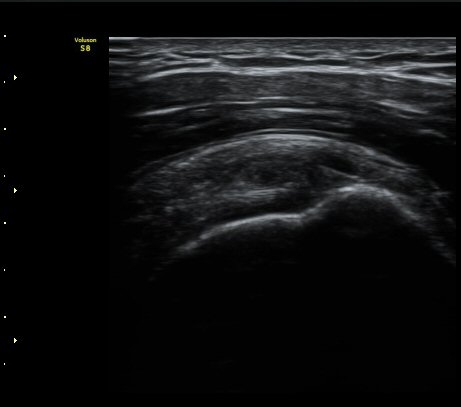

±Ø»ó°Ç Á¾´Ü¸é°Ë»ç¿¡¼­ ´ë°áÀý °Ç ºÎÂøºÎ¿¡ Àú¿¡ÄÚ °Ç °á¼ÕÀÌ °üÂûµÊ

(focal hypoechoic defect of ssupraspinatus tendon at greater tuberosity with

longitudinal scan of subscapularis tendon) »çÁø 4, 5, 6